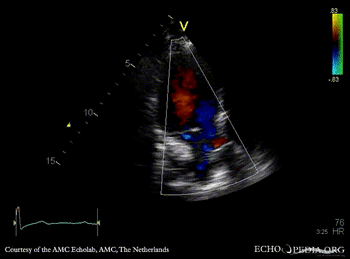

Subvalvular membrane

A3CH with Color Doppler: high velocity flow in LVOT Continuous-wave Doppler signal of flow in LVOT